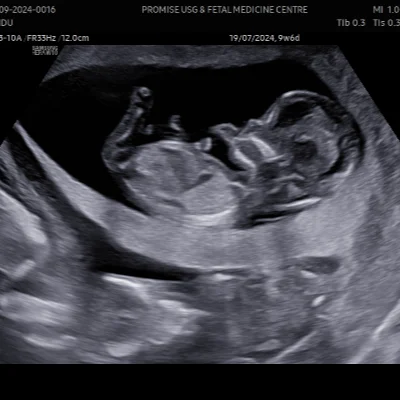

Obstetric Ultrasound

We specialize in obstetric imaging to support mothers and babies throughout pregnancy

Early Pregnancy Scans

Confirm gestational age and fetal viability

Fetal Growth Scans

Track development and detect anomalies

NT Scan

Nuchal translucency screening for chromosomal risks

Level II / TIFFA Scan

Detailed anomaly scan to assess fetal organs and structure

Our team ensures a calm, respectful environment for expectant mothers, with clear communication and compassionate care at every stage.